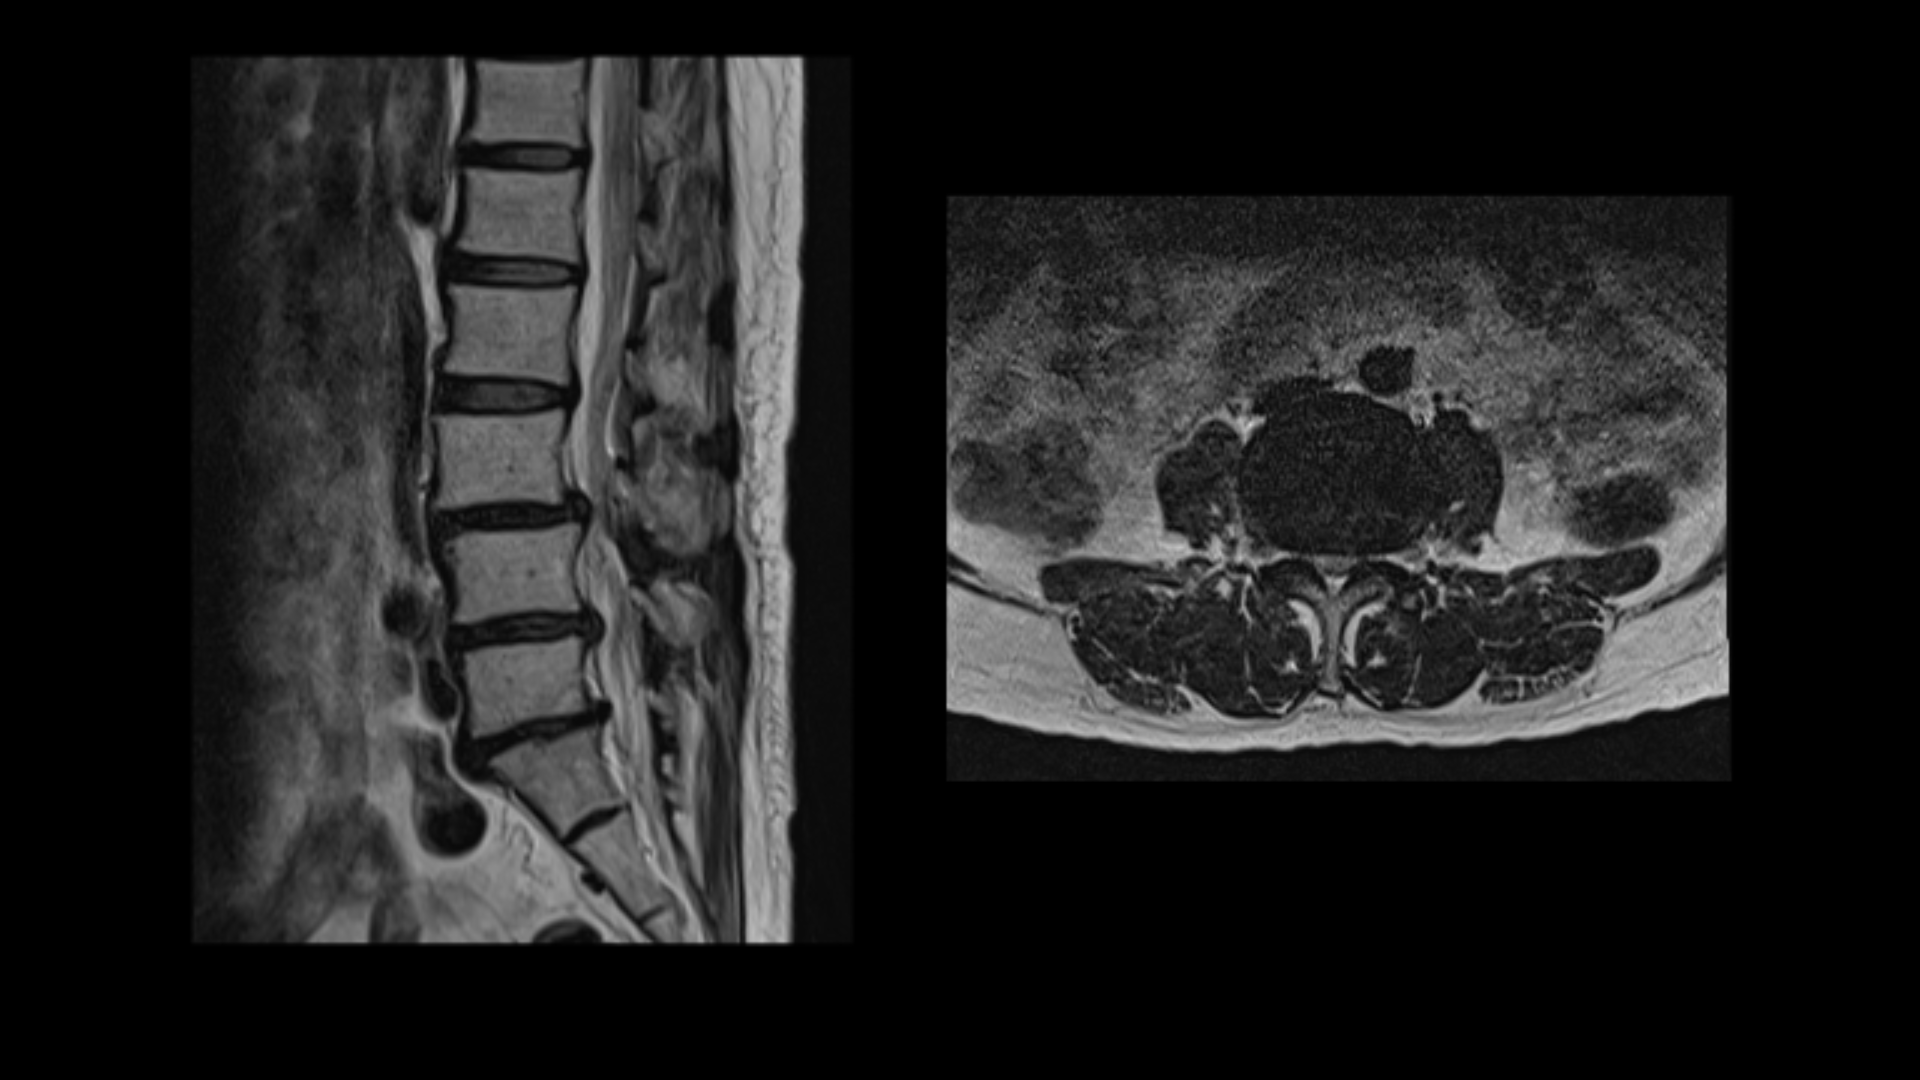

이분 MRI를 보면 3마디에 퇴행성디스크가 밀려 나와 있습니다.

또 3번 4번에는 척추전방전위증이 있습니다.

이 전방전위증 때문에 척추관에 중심성 협착도 있습니다.

4번 5번 디스크가 중앙에서 우측으로 약간 밀려 나와있고

>또 5번 1번에서는 신경이 빠져나가는 오른쪽 추간공이 약간 좁아져 있습니다.

그런데 이분 허리 MRI를 자세히 보면 딱히 신경이 아주 극심하게 눌린 곳도 없습니다.

신경이 조금 눌릴 수는 있어도 심각해 보이지는 않습니다.

신경구멍이 지나가는 길이 여러 가지 퇴행성 변화로 조금씩은 좁아져 있지만 굳이 수술로 특히 여러 마디의 나사를 박는 수술까지 해가며 신경압박을 해소해야 할 정도의 심한 신경눌림은 보이지 않는 겁니다.